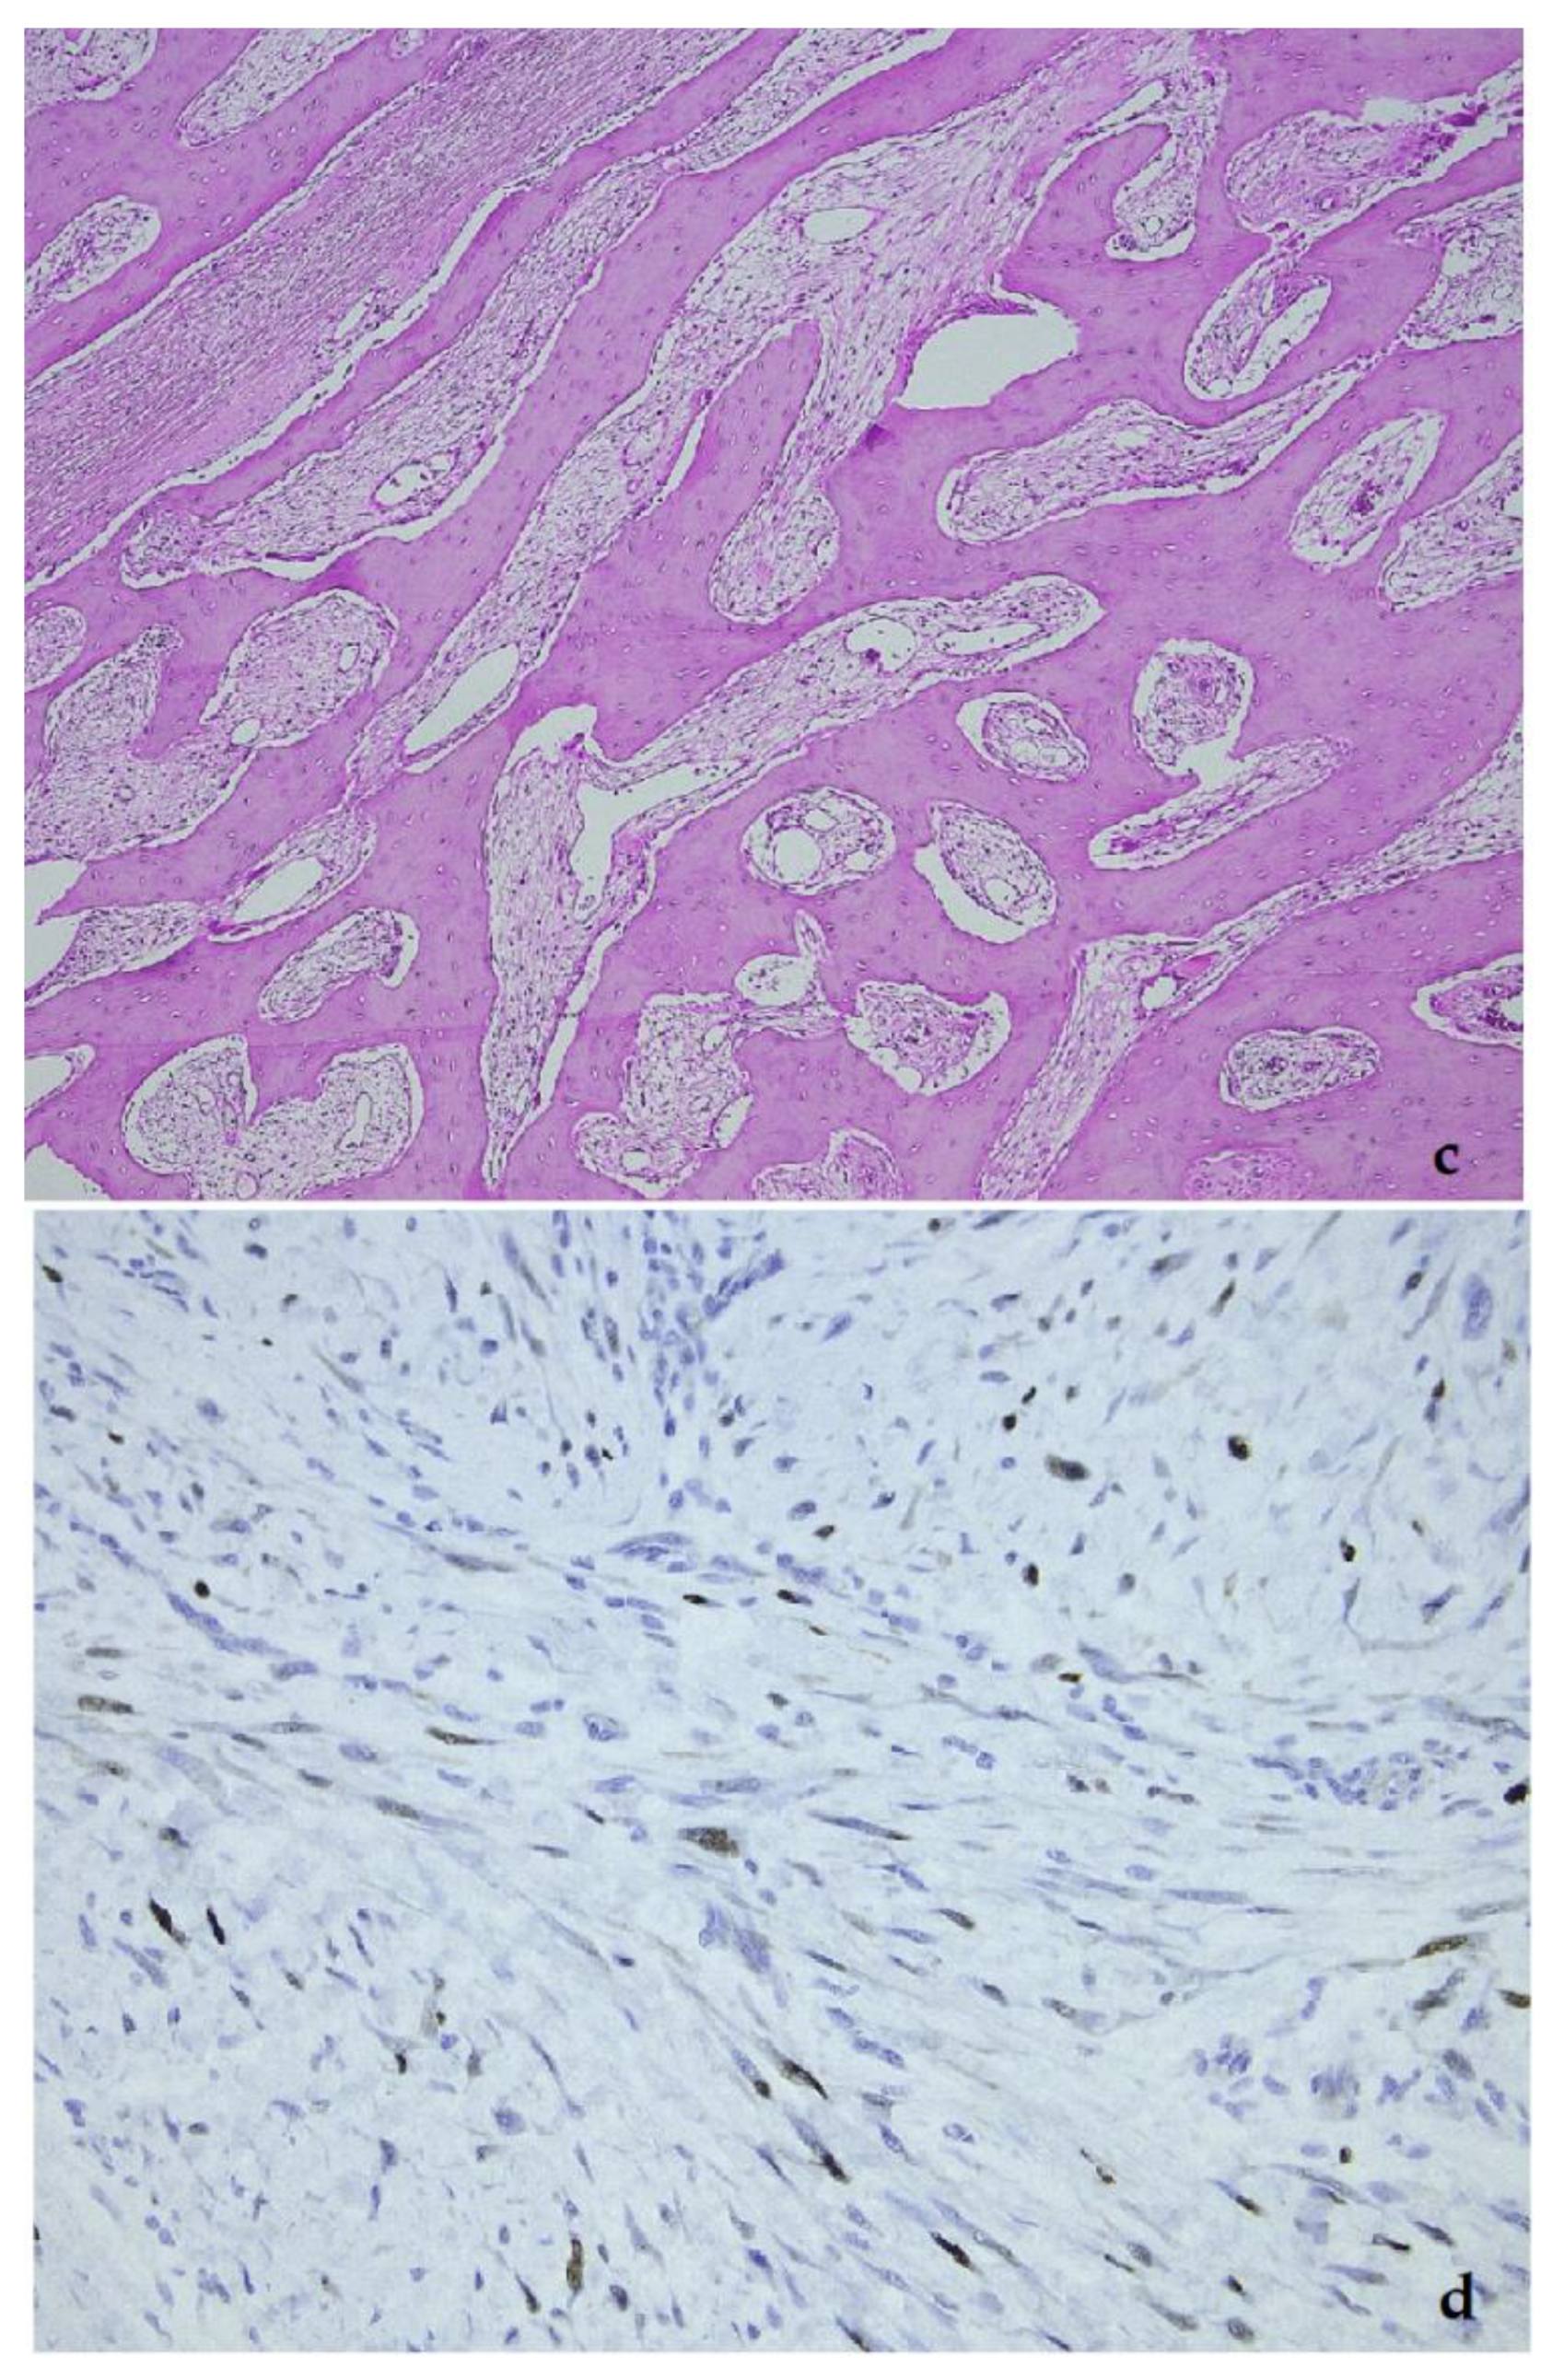

4. Intimal Sarcoma